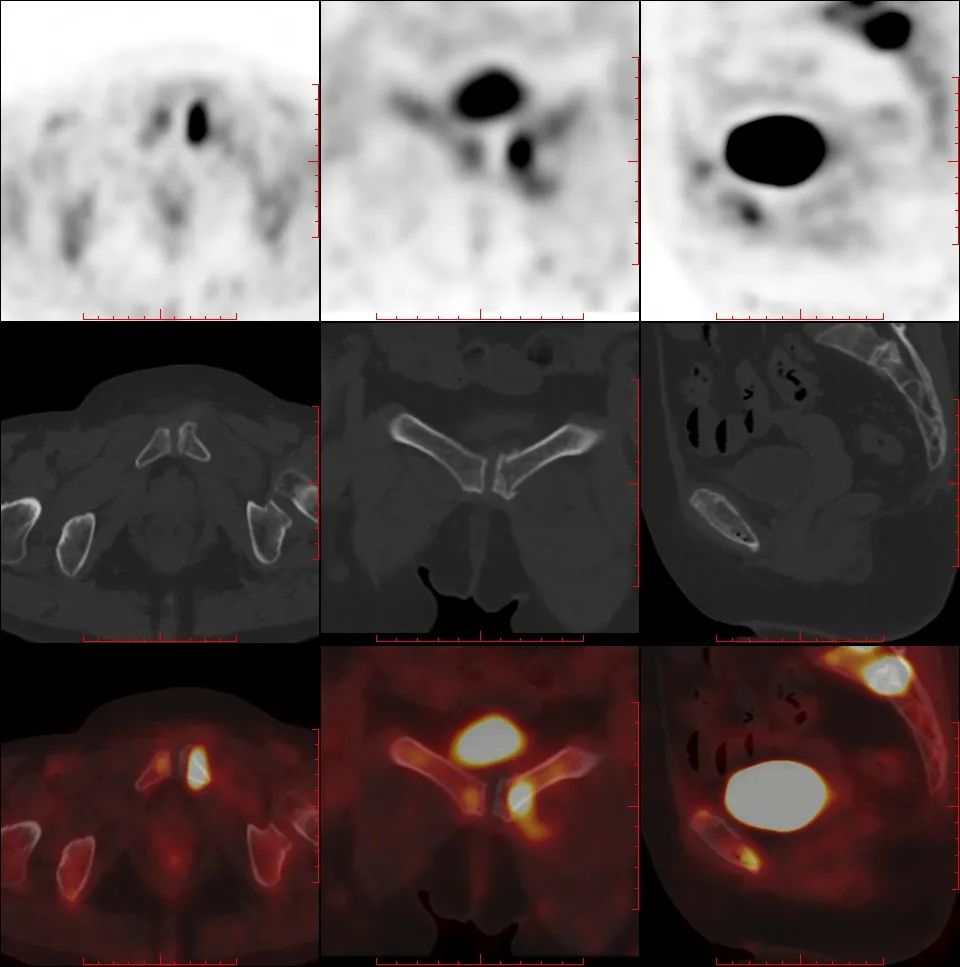

骶骨机能不全骨折 PET/CT 表现

骶骨机能不全骨折的典型 18F-FDG PET/CT 表现为平行于骶髂关节的骨折线伴 FDG 摄取轻中度增高,PET/CT 显示病变的 FDG 摄取特征及形态学改变与转移瘤的鉴别诊断有重要价值。

女,55 岁,宫颈癌放化疗后 5 年发生骶骨机能不全骨折。PET/CT 骶骨横断面(A)、冠状面(B)显示双侧骶骨翼平行于骶髂关节骨折线,放射性摄取弥漫性轻度增高,沿骨折线处为著(箭);矢状面(C)显示骶骨体横行硬化骨折线,轻度 FDG 摄取(箭)